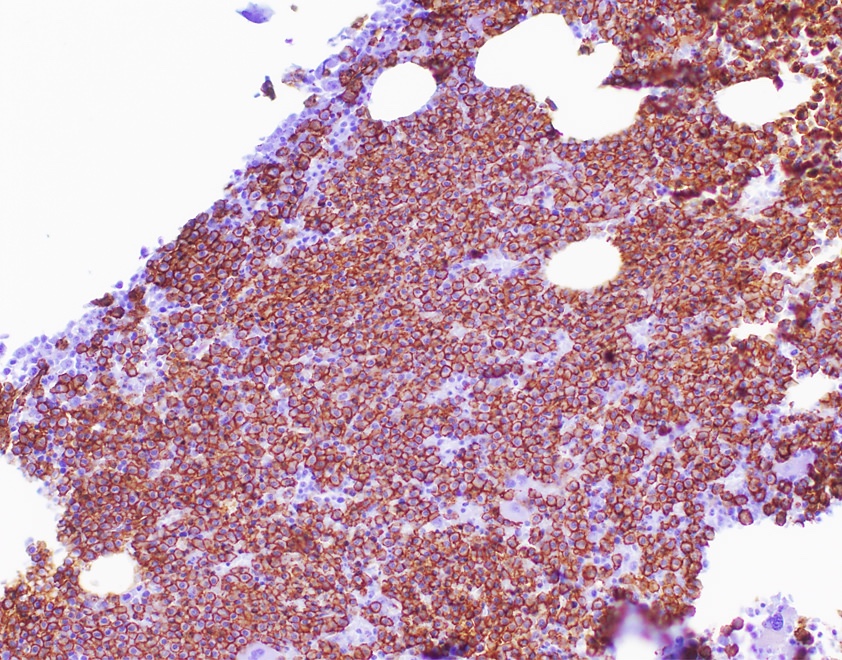

- IHC to quantify plasma cells (CD138), stains for Ig kappa and lambda to establish clonality

Positive stains

- CD38, CD138, VS38c

- MUM1, EMA, CD79a (variable)

- May have aberrant expression of CD56 (75 - 80%), CD200 (60 - 75%), CD28 (~40%), CD117 / KIT (20 - 35%), CD20 (10 - 20%), CD52 (8 - 14%), CD10 and occasional myeloid or monocytic markers; may correlate with cytogenetics in some cases (Leuk Lymphoma 2015;56:426, Cytometry B Clin Cytom 2016;90:61)

- Monoclonal light chain

- Cyclin D1 positive in presence of t(11;14)(q13;q32), variable expression levels with hyperdiploidy or 11q13 amplification (Blood 2004;104:1120)

- t(11;14) translocation associated with expression of B cell markers on the clonal plasma cells including CD19, CD20, CD79a (Leuk Res 2013;37:1251)

Flow cytometry description

- Monotypic cytoplasmic Ig and usually lack surface light chain

- Express CD38, CD138, often CD56+ or CD117+; may have partial CD45, usually negative for CD20, CD19 and CD10 (Cytometry B Clin Cytom 2016;90:61)

- Exception in myeloma with t(11:14) where plasma cells more often express B cell markers including CD19 and CD20